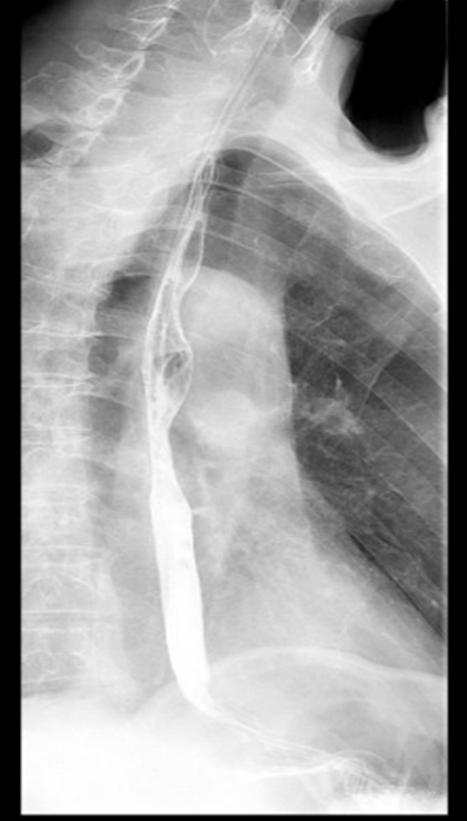

72岁的陈先生(化名),2024年8月开始出现进食梗阻及呛咳,我院增强CT显示是局部中晚期胸中段食管癌,怀疑食管瘘形成。消化道造影证实了这一猜想。胃镜发现胸中段食管鳞癌伴有管腔狭窄。经我院食管癌多学科专家会诊,建议留置营养管,一般情况改善后先行全身治疗,适时局部治疗。患者入院后行内镜下胃管置入术,抗感染治疗后给予全身治疗,经治疗后,患者病情得到持续好转,生存时间已超过16个月,且食管瘘愈合,拔除营养管后,患者实现了经口进食,生活质量显著提升。

治疗后肿瘤管腔改善,造影剂通畅无外漏,瘘口完全愈合